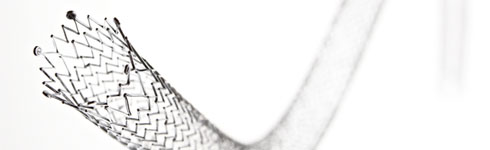

Vascular Stents

Vascular stents are an interesting example of how engineers continuously refine a concept over several product generations. The technology has evolved from a wire mesh tube to hold open an artery to more sophisticated devices – including the drug-eluting stents that have emerged over the past decade.